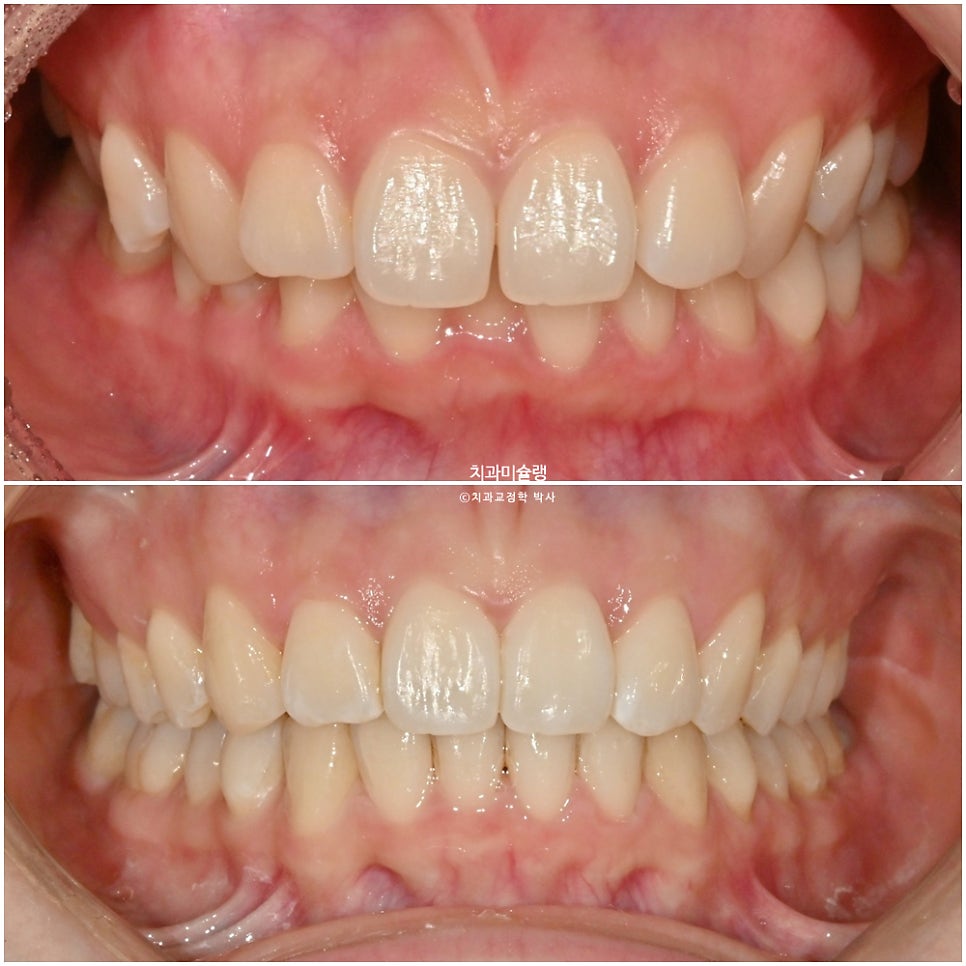

초진 상태 – 2025년 여름

2025년 여름, 앞니 부분교정을 하고싶어 온 환자분 입니다.

중심선 불일치가 보이며 아랫니가 거의 안보일 정도의 과개교합 입니다.

윗니중 가운데 앞니가 튀어나와있습니다.

25년 6월부터 10월까지, 3개월 반에 걸쳐 14개 장치를 모두 낀 후 모습입니다.

과개교합이, 중심선, 배열의 개선이 보입니다.

최종 치료 결과 – 2026년 3월

어금니 교합은 물샐틈 없는 1급 교합관계를 보입니다.